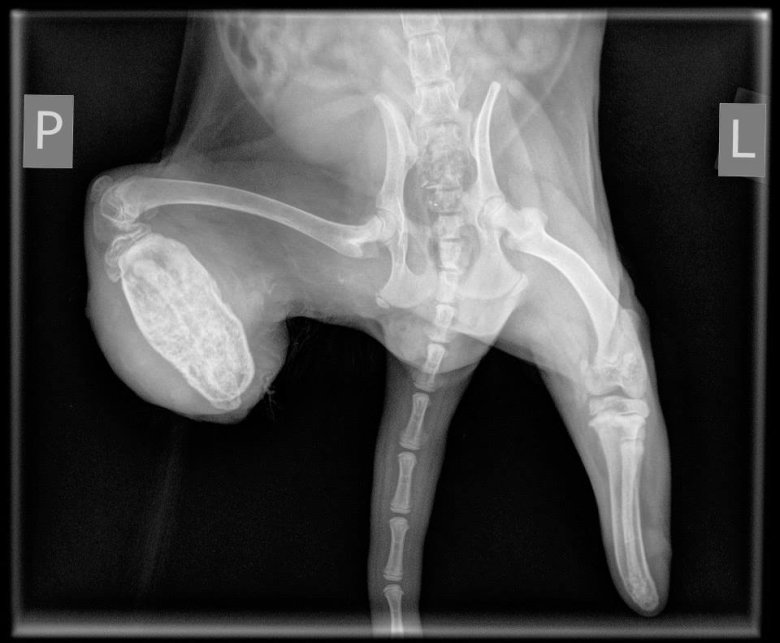

Często widujemy lisy z kontuzjami kończyn, które zapadają im się w kraty. Nierzadko oglądamy zwyrodnienia stawów. Brak nóg to rzadki przypadek. Rzadki przede wszystkim dlatego, że utrata kończyn zwykle kończy się śmiercią przez wykrwawienie. Przyczyną jest najczęściej odgryzienie ich przez matkę, która bądź próbuje ratować szczeniaka, którego łapy zablokowały się w otworach klatki, bądź wykazuje problemy behawioralne wynikające z patologicznych warunków bytowania.

Zwierzęta trafiły pod opiekę weterynarza oraz wolontariuszy. Jest szansa, że po podjęciu leczenia i niezbędnych operacjach otrzymają szansę na nowe życie. Wszystko jednak w rękach wójta gm. Kościan, który musi zatwierdzić słuszność podjętej interwencji. Stowarzyszenie Otwarte Klatki jest jednak pewne, że zwierzęta nie wrócą na fermę i zwraca się z prośbą o wsparcie ich leczenia. Można to zrobić wpłacając nawet symboliczną dotację przez stronę: http://www.otwarteklatki.pl/wplac-dotacje/, tytuł przelewu: LISY